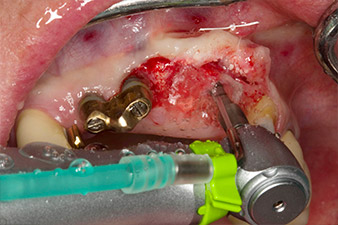

Sección de la rosca con el contra-ángulo WS-75 L

Imagen. 3: Sección de la rosca con el contra-ángulo WS-75 L con una transmisión de 20:1 (programa P4). En este caso, resultan útiles el alto torque del Implantmed, el sistema de sujeción hexagonal para una transmisión segura de la fuerza y la inversión automática del sentido de giro cuando hay una alta resistencia.